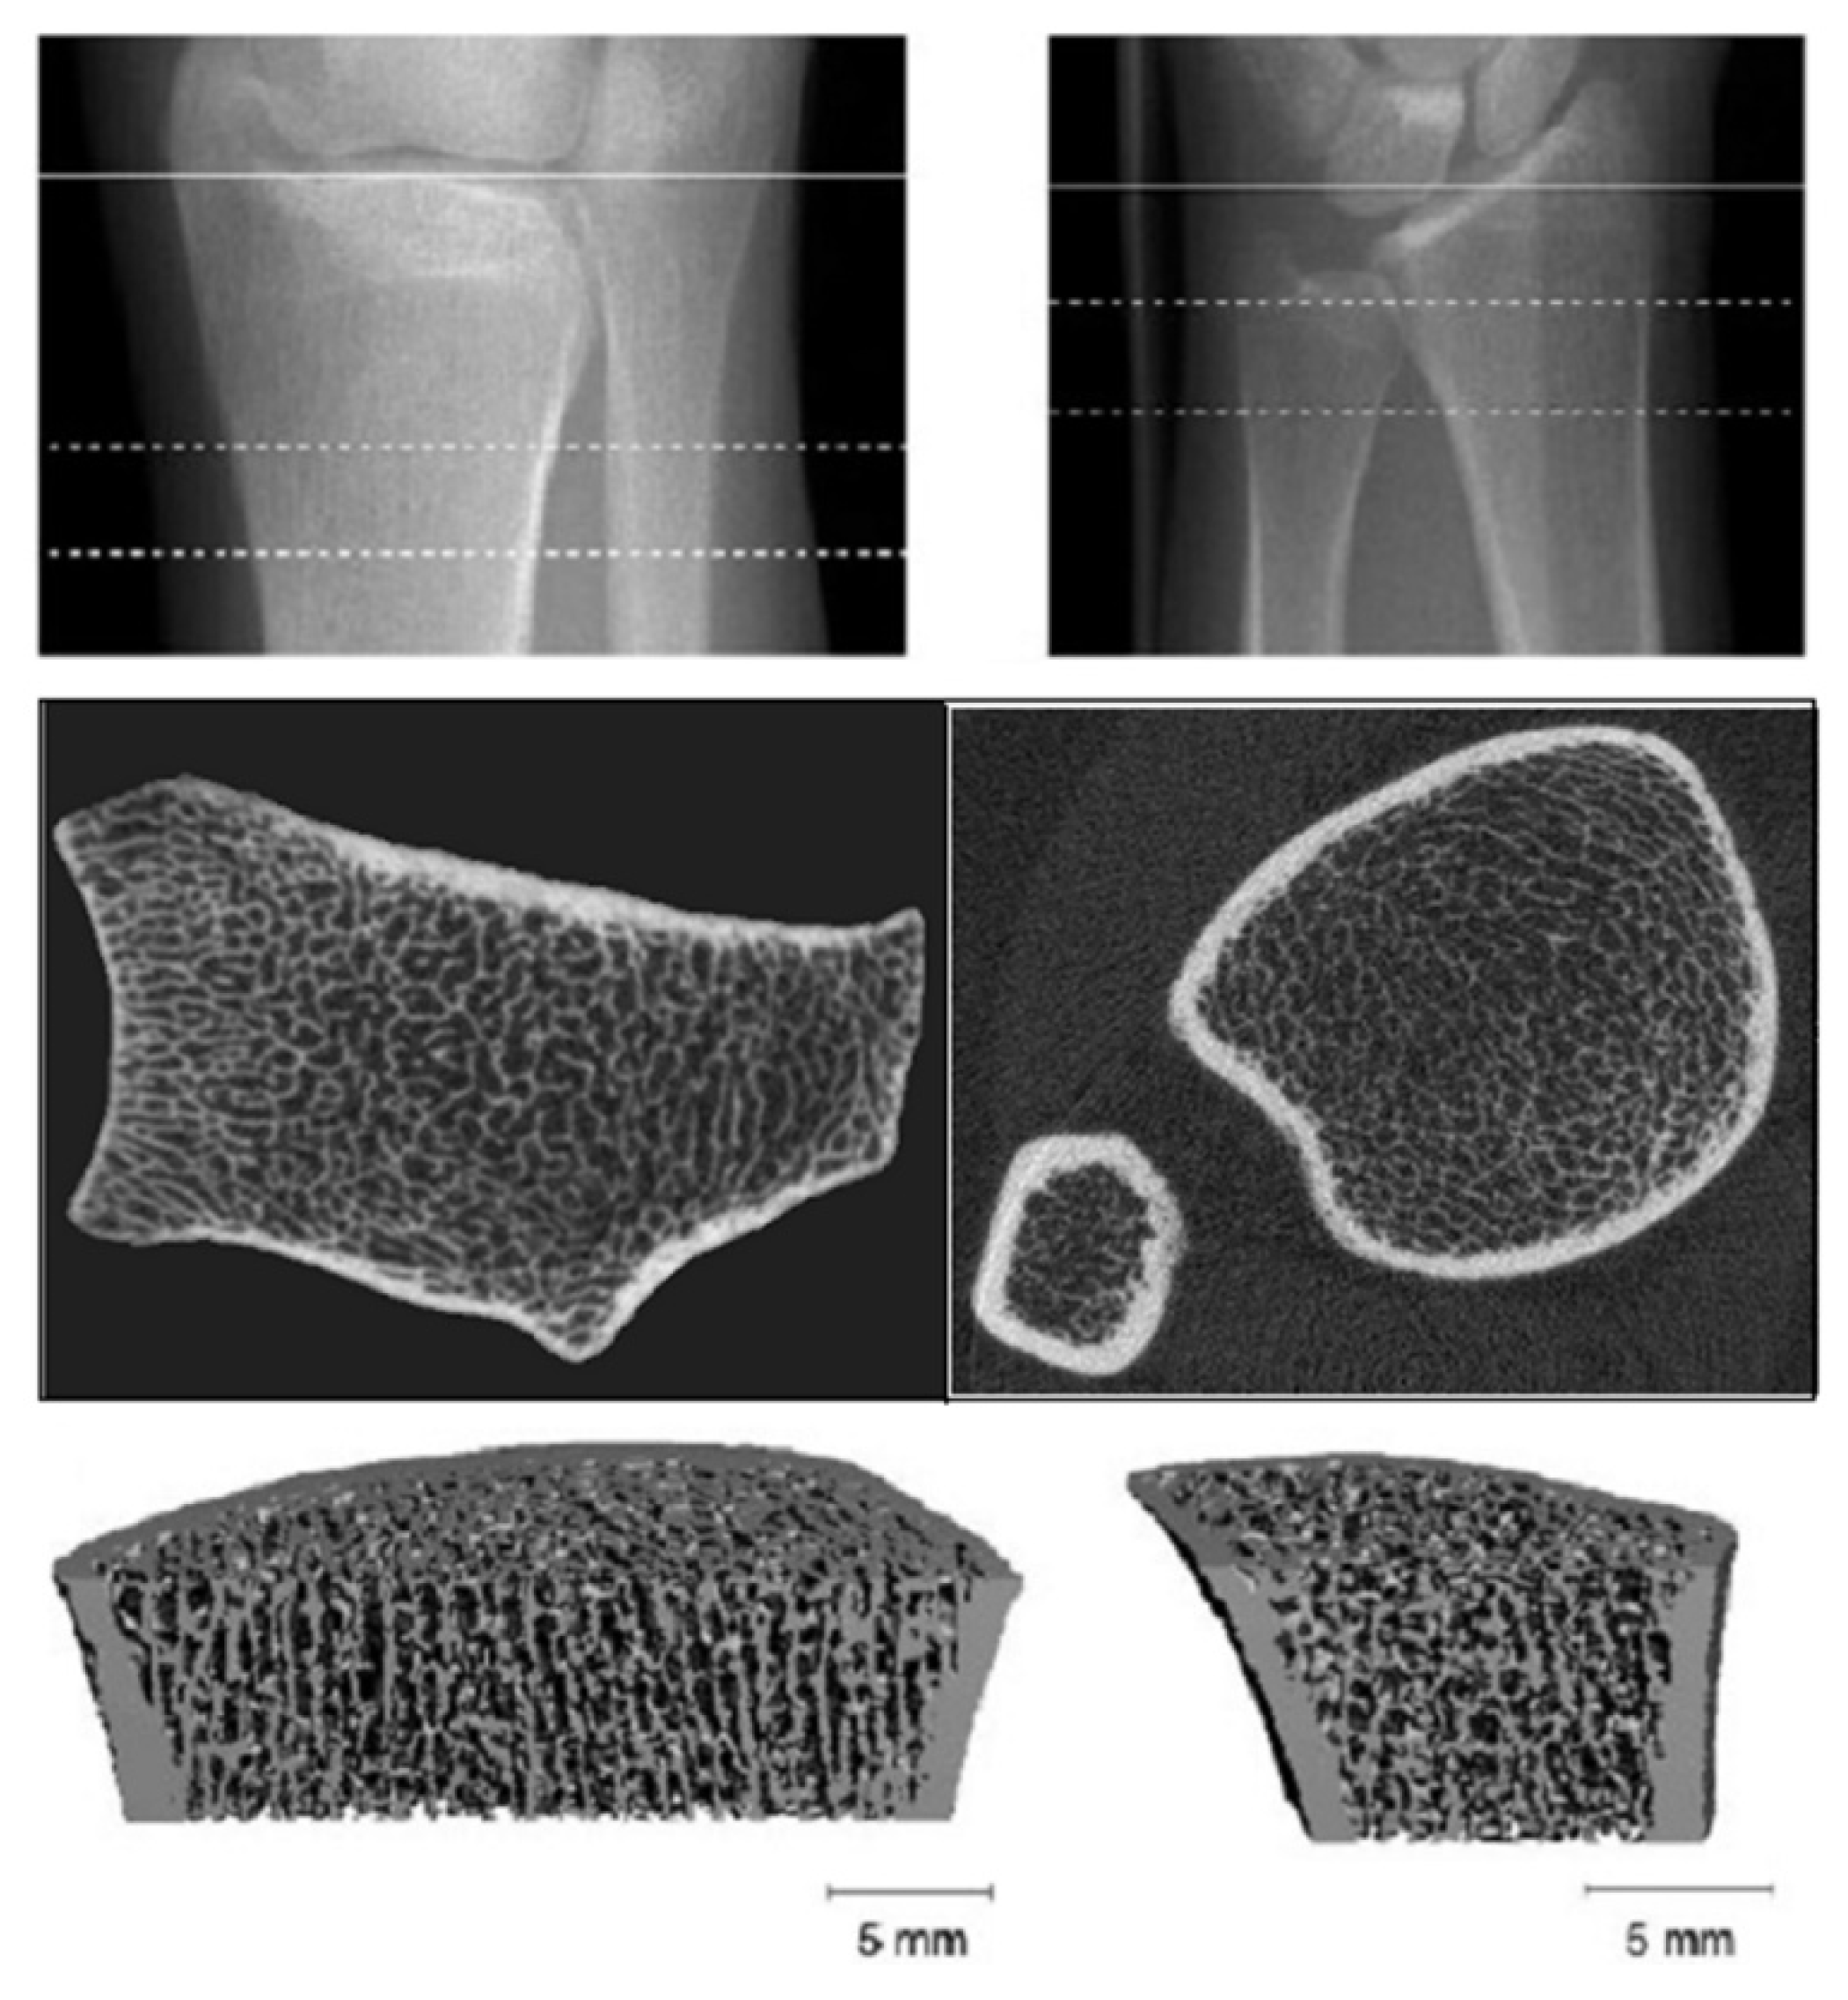

3.6. High Resolution-Peripheral Quantitative Computerized Tomography (HR-pQCT)

- Ramalho, J.; Marques, I.D.B.; Hans, D.; Dempster, D.; Zhou, H.; Patel, P.; Pereira, R.M.R.; Jorgetti, V.; Moyses, R.M.A.; Nickolas, T.L. The trabecular bone score: Relationships with trabecular and cortical microarchitecture measured by HR-pQCT and histomorphometry in patients with chronic kidney disease. Bone 2018, 116, 215–220. [Google Scholar] [CrossRef]

- Cejka, D.; Patsch, J.M.; Weber, M.; Diarra, D.; Riegersperger, M.; Kikic, Z.; Krestan, C.; Schueller-Weidekamm, C.; Kainberger, F.; Haas, M. Bone microarchitecture in hemodialysis patients assessed by HR-pQCT. Clin. J. Am. Soc. Nephrol. 2011, 6, 2264–2271. [Google Scholar] [CrossRef] [PubMed]

- Negri, A.L.; Del Valle, E.E.; Zanchetta, M.B.; Nobaru, M.; Silveira, F.; Puddu, M.; Barone, R.; Bogado, C.E.; Zanchetta, J.R. Evaluation of bone microarchitecture by high-resolution peripheral quantitative computed tomography (HR-pQCT) in hemodialysis patients. Osteoporos. Int. 2012, 23, 2543–2550. [Google Scholar] [CrossRef]

- Sharma, A.K.; Toussaint, N.D.; Masterson, R.; Holt, S.G.; Rajapakse, C.S.; Ebeling, P.R.; Mohanty, S.T.; Baldock, P.; Elder, G.J. Deterioration of Cortical Bone Microarchitecture: Critical Component of Renal Osteodystrophy Evaluation. Am. J. Nephrol. 2018, 47, 376–384. [Google Scholar] [CrossRef]

| HR-pQCT | Trabecular architecture Volumetric BMD | Hip, distal radius, distal tibia | Secondary Hyperparathyroidism | All and research |